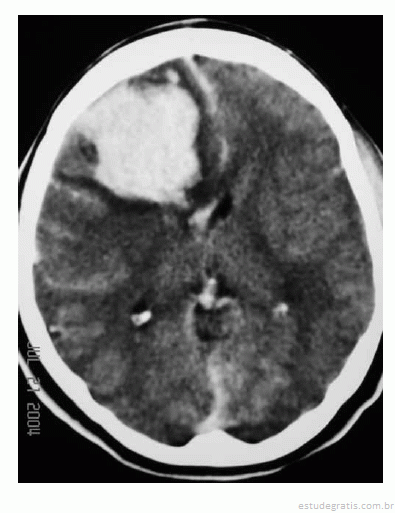

Uma mulher de 29 anos de idade teve sua gestação interrompida com 35 semanas, mediante parto cesariano, por ter apresentado quadro compatível com a doença hipertensiva específica da gravidez. No quinto dia de pós-operatório, apresentou importante dor de cabeça seguida de crises convulsivas; na avaliação laboratorial, foram atestadas plaquetopenia e alteração da função hepática. Ela foi levada à unidade de terapia intensiva, onde o plantonista observou hemiparesia esquerda e solicitou uma tomografia de crânio sem contraste, que é reproduzida abaixo.

Com base nessas informações, julgue os itens que se seguem.

Para essa paciente está contraindicada a punção lombar para alívio da cefaleia.Comentários